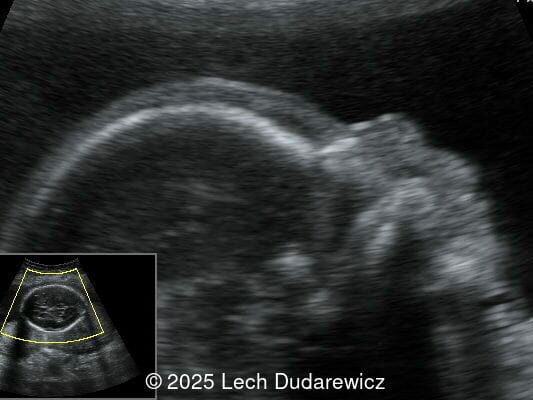

Ultrasound revealed a single live fetus with 46,XY karyotype. Biometric measurements demonstrated discrepancies with the femur and tibia length lagging significantly at 19 weeks and notable shortening and bowing of the femur, tibia, and fibula. The findings were consistent with skeletal dysplasia.

Structural anomalies were observed in multiple organ systems. The fetal skeleton showed hypoplastic iliac bones, rib deformities, hypoplastic scapulae, and excessive cervical spine lordosis. The fetal hands exhibited abnormal alignment of the fingers with restricted movement, and both feet were clubbed. Subcutaneous edema was noted over the forehead and occiput with a small cystic hygroma, along with increased nuchal fold thickness at 5.6mm, indicative of soft tissue edema. Additional abnormalities included mild pyelectasis. The fetal stomach appeared nearly empty, likely reflecting impaired swallowing or associated anomalies. Polyhydramnios was also noted. External male genitalia appeared normal. Cardiac evaluation revealed multiple echogenic foci within the left ventricle and an atrioventricular septal defect. While the heart's overall structure and function were otherwise normal, these findings added to the overall suspicion of a syndromic condition.

Prenatal ultrasound is a crucial tool for early diagnosis, enabling appropriate counseling and perinatal management of campomelic dysplasia. Key skeletal abnormalities include significant shortening and bowing of long bones, particularly the femur and tibia. In a study by Mansour et al, the lower extremities are primarily involved with minimal bowing of the humerus, ulna, and radius. Bowing often presents with associated angulation, giving rise to the term "campomelia," meaning bent limbs in Greek. Hypoplastic iliac bones and scapulae are hallmark features, while rib anomalies such as deformities or reduced number, typically 11 pairs, may also be observed. Additionally, the chest may be narrow and bell-shaped. Cervical spine abnormalities, including excessive lordosis or kyphosis, are often present and may contribute to postnatal respiratory complications. These findings are important for risk stratification and delivery planning.